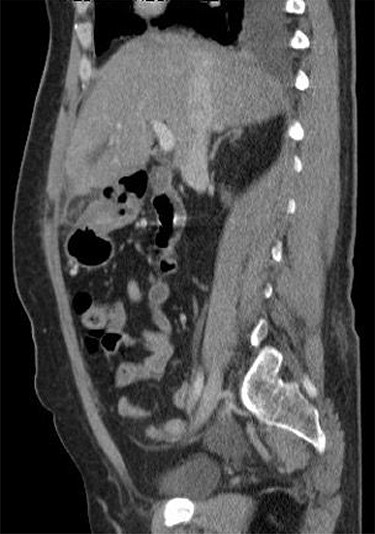

A 53-year-old fit and well woman presented to the emergency department with acute epigastric and right hypochondrium pain with a positive Murphy’s sign of the abdomen. The patient was anicteric and apyrexial. Blood tests performed revealed a white cell count of 13.6 × 109/L and a C-reactive protein of 110 U/L. Liver function tests, amylase and urea and electrolytes were unremarkable. A working diagnosis of acute cholecystitis was made and the patient commenced on intravenous fluids and intravenous antibiotics. Abdominal ultrasound was performed, which demonstrated no gallstones nor choledocholithiasis and was essentially normal. Given the raised inflammatory markers and persistent abdominal pain, CT scan was performed (Fig. 1). This revealed a 32 × 22-mm oval-shaped fat density lesion with peripheral hyper attenuation adjacent to the falciform ligament, representing intraperitoneal focal fat infarction of the fatty appendage of falciform ligament. Sagittal reconstruction showed a central hyperdense thrombosed vessel secondary to torsion of the falciform ligament (Fig. 2).

Contrast-enhanced CT scan shows a 32 × 22-mm oval-shaped fat density lesion with peripheral hyperattenuation and central hyperdense dot adjacent to falciform ligament. There is surrounding oedema and inflammation. Gall bladder is noted to be unremarkable. Features represent intraperitoneal focal fat infarction of fatty appendage of falciform ligament.

Sagittal reconstruction redemonstrates central hyperdense thrombosed vessel secondary to torsion